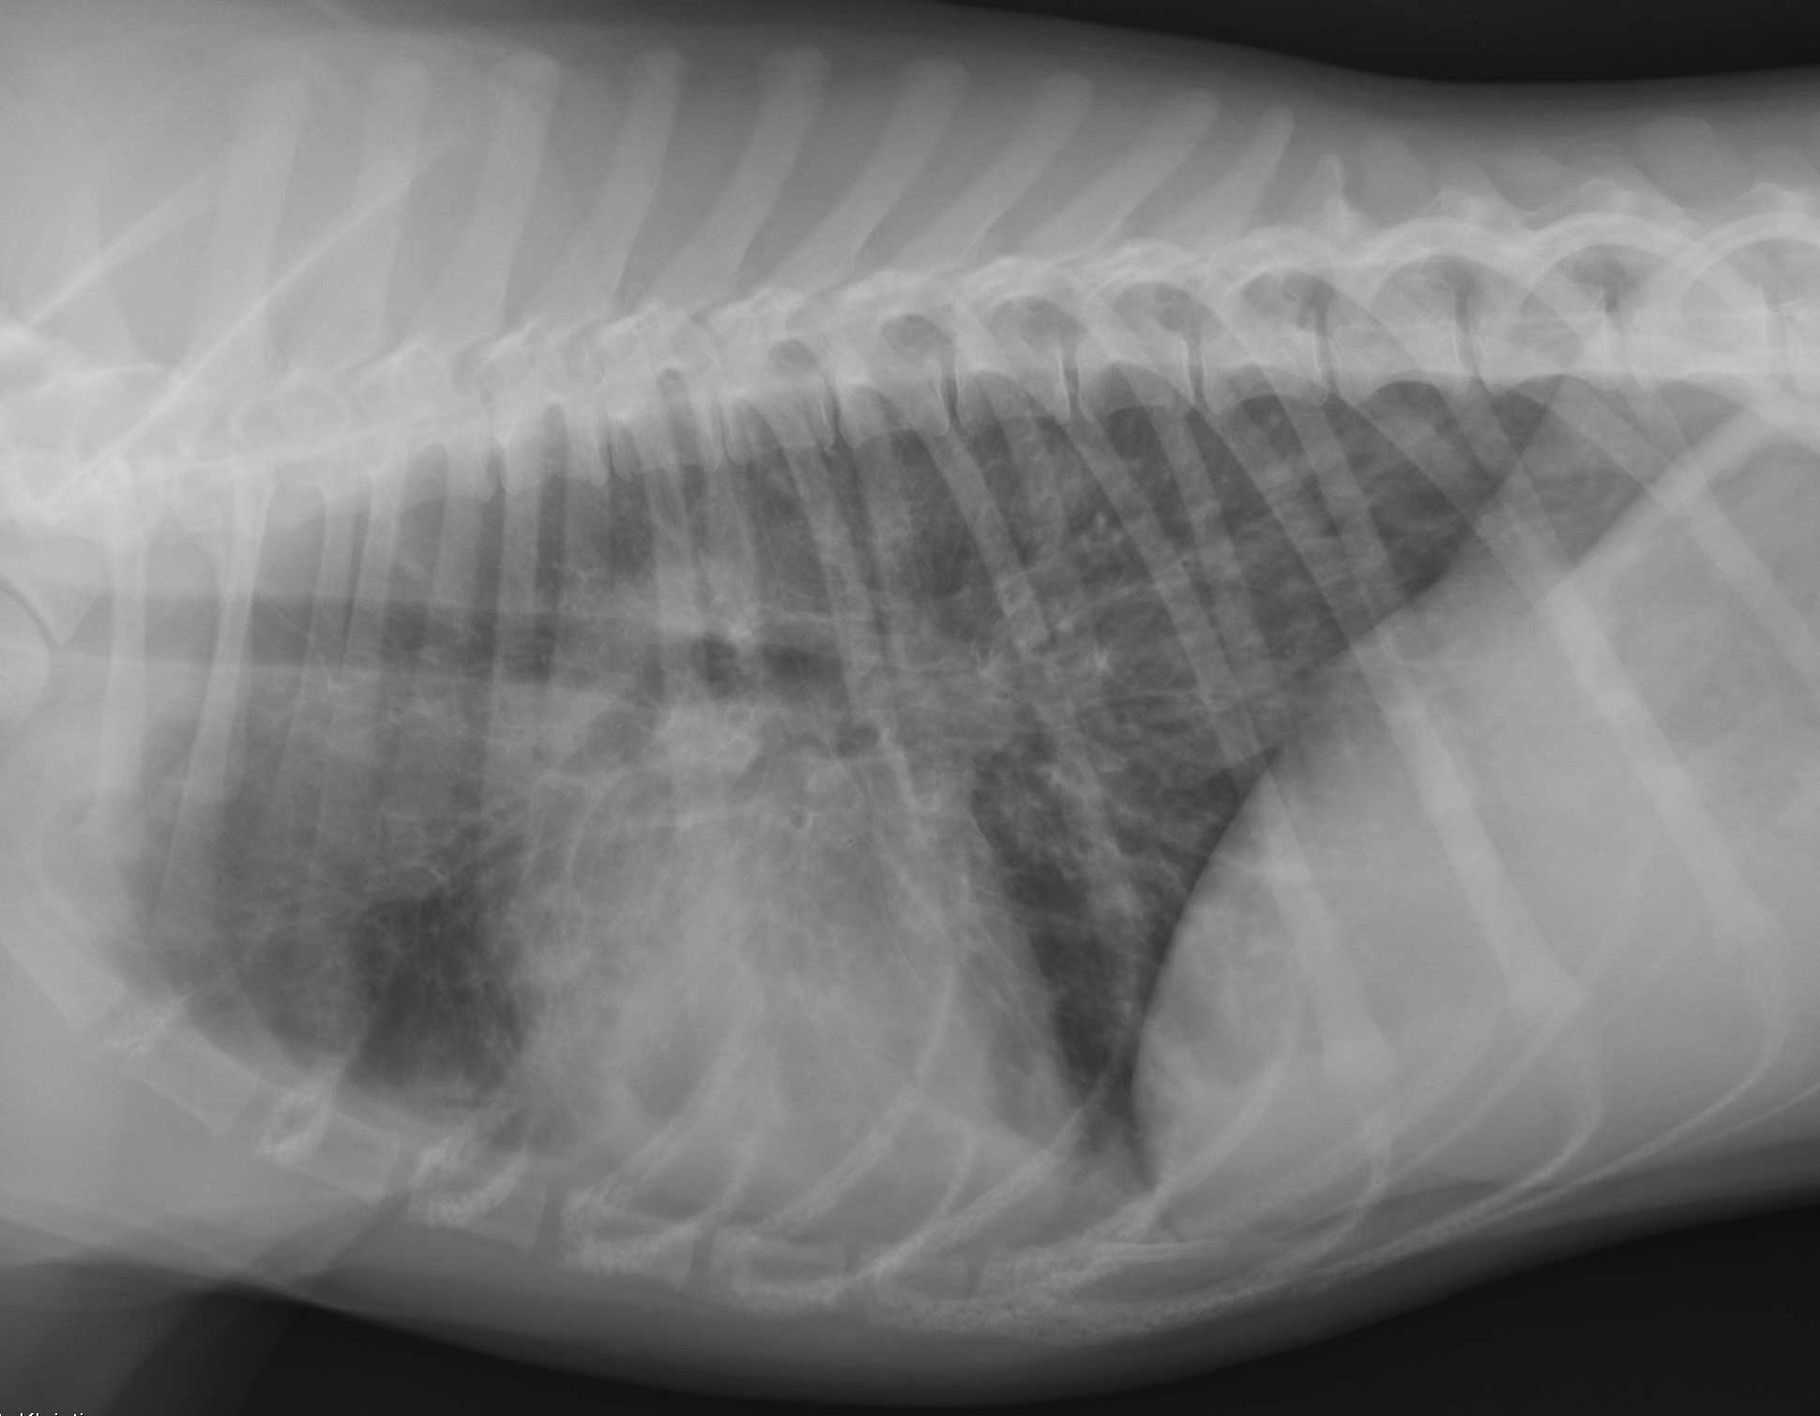

Lungenzeichnung made easy! vetradiologies Webseite!